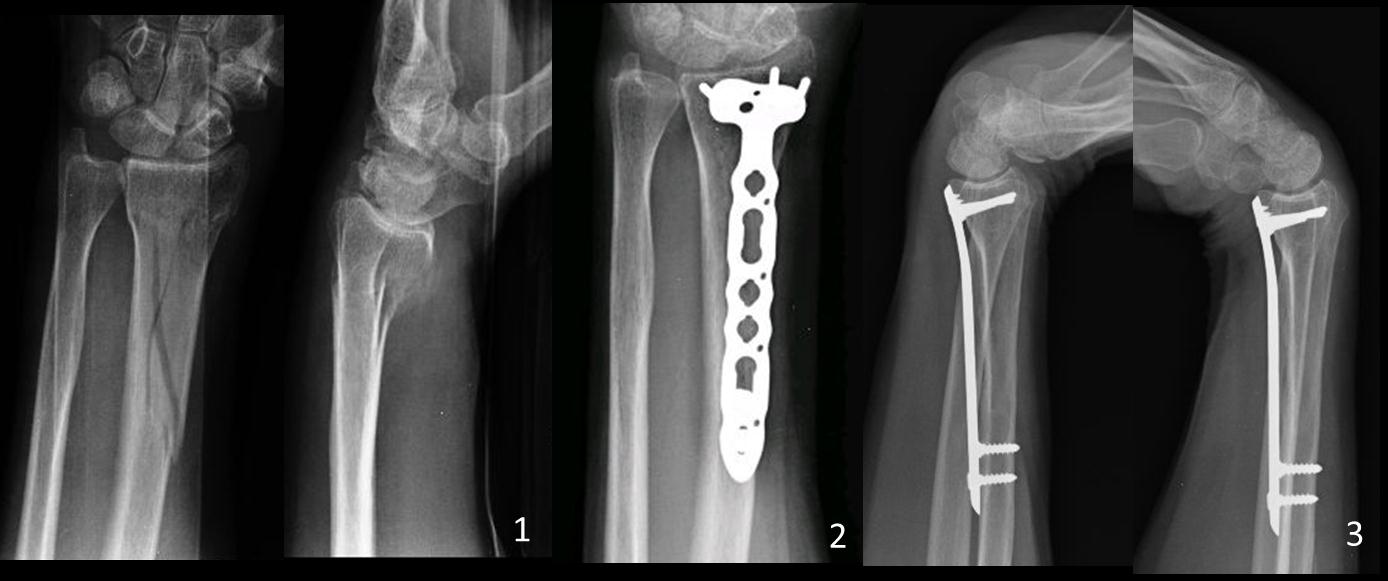

Introduction: Purpose:To evaluate objective and subjective outcomes after closed reduction and minimally invasive volar locked T plate osteosynthesis for distal radius fractures with metaphyseal involvement.MethodsWe retrospectively evaluated six patients treated by minimally invasive volar locked T plate osteosynthesis for unstable extra-articular or partial articular distal radius fractures with metaphyseal involvement between 2007-2012. Age averaged 40, 6 years. All were closed fractures classified as type 23A3 (n: 5) and 23B1 (n: 1) according to the AO/OTA system.  Indirect reduction was performed. Two volar small incisions were made; a volar locked compression T plate was introduced in the sub-muscular plane, under radioscopic guidance. Analysis included radiological parameters (volar angulation, radial inclination, and radial height); range of motion and strength. Subjective results were assessed using DASH Score and Visual Analogue Scale.ResultsAll fractures healed within 2, 3 months. Radiographic outcomes showed no difference between the first postoperative control and the last Rx at one year of follow up. Flexion and extension averaged 70° and 60°, pronation and supination 79° and 80°. Grip Strength 78, 4%. DASH Score 19, 84 and VAS 1, 5 points.ConclusionsMinimally Invasive technique decrease surgical injury and complications (infections and re fractures). It is an option in patients with metaphyseal comminution severe soft tissue injuries and high energy trauma. Small incisions away from the fracture site preserve soft tissues, bone biology and improve healing. Percutaneous volar LCP allows obtaining stable fixation and restoring distal radius anatomy in radius fractures with metaphyseal involvement. It is technically demanding procedure. The most common problem is bone misalignment.